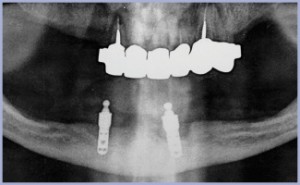

Paziente femminile, di anni 60, non fumatrice con residui radicolari da bonificare. Vista la TAC e l’ortopantomografia (figg. A, B), si decide per l’inserimento di 5 impianti post-estrattivi immediati con apertura di ampio lembo per estrazioni atraumatiche dei residui radicolari (figg. 1, 2, 3). Si inseriscono impianti Leone diametro 3,3 per 12 mm in sede 12, 11, 22; diametro 3,3 per 14 mm in sede 23; diametro 4,1 per 10 mm in sede 25 (figg. 4, 5, 6, 7, 8).

- Fig. B